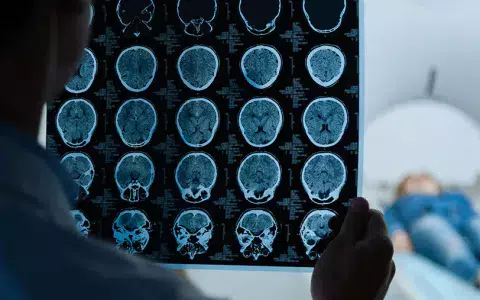

Tauti voidaan todeta aivojen magneettikuvauksessa otsa- ja ohimolohkojen alueelle painottuvana aivokuoren poimujen paksuuntumisena, eli pakygyriana, joka johtaa tautigeenin jäljille.

Suomesta on löytynyt peittyvästi periytyvä aivosairaus, joka aiheuttaa lievää tai keskivaikeaa älyllisen kehityksen viivästymistä. Sairaus näkyy aivojen magneettikuvauksessa otsa- ja ohimolohkojen alueelle painottuvana aivokuoren poimujen paksuuntumisena, jos sitä osataan epäillä. Sen jälkeen tauti voidaan varmistaa geenitestillä.